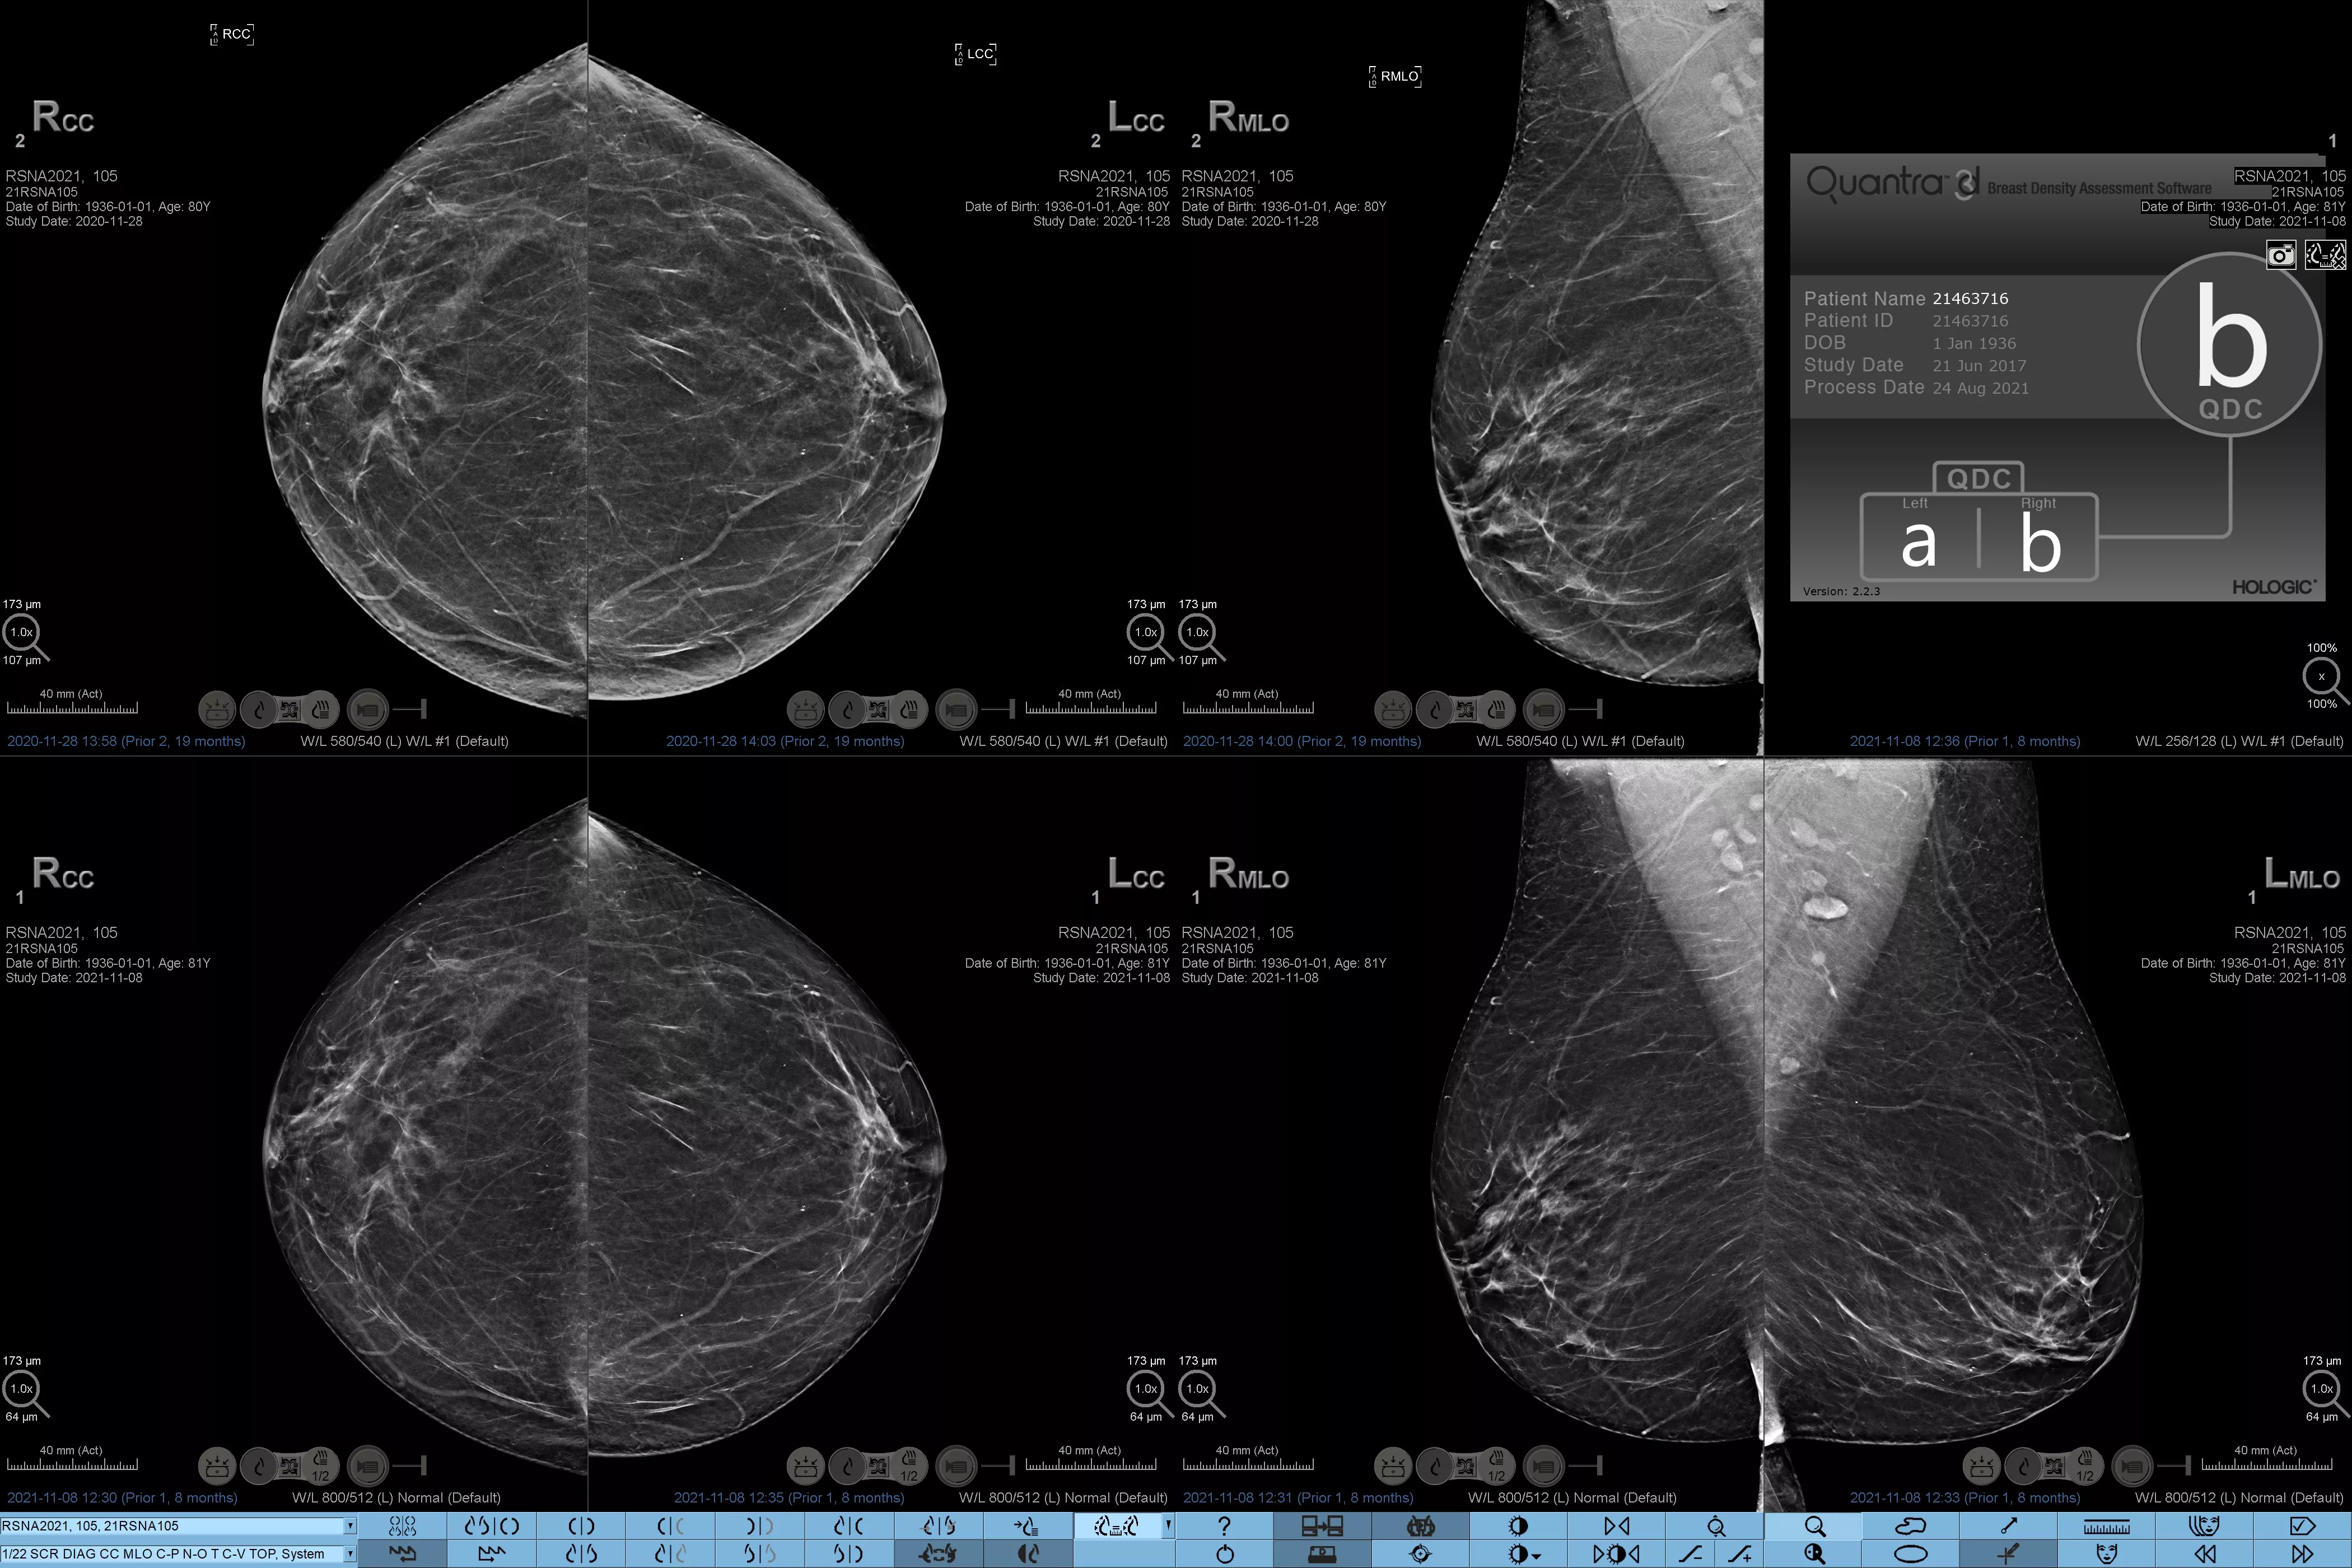

乳腺密度分析の標準化

乳腺濃度が高いと、女性の乳がんリスクが高まることが知られています1。したがって、正確でバイアスのない分析が極めて重要です。機械学習を活用する Quantra テクノロジーソフトウェアは、2D™ 画像とトモシンセシス画像の両方を分析して乳腺密度の割合を分類します。米国放射線医学会 (ACR) BI-RADS アトラス第 5 版のガイドラインに従って、乳房を 4 つの乳房組成のカテゴリーに分類します2

乳房組織の質感とパターンの分析に基づいて乳腺密度のカテゴリーを割り当てる客観的な機械学習アルゴリズム。

*スコアは、米国放射線学会 (ACR) BI-RADS アトラス第 5 版の改訂ガイドラインに沿って、ACR BI-RADS カテゴリーに基づいています。密度を決定する際に、体積と比較してパターンと質感を考慮します。